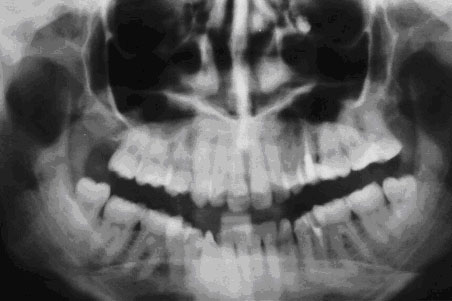

Перфорация верхнечелюстной пазухи слева (отпечаток с ортопантомограммы)

Перфорациядонной области верхнечелюстной пазухи может случится в процессе удаления верхних зубов. В основном это произойдет при удалении больших, реже маленьких зубов. Это случается потому, что анатомическое строение имеет свои особенности, которые затрагивают корни этих зубов и дно пазухи, находящейся в верхней челюсти.

При пневматическом типе образования пазухи верхние части корней больших и малых зубов отделены от дна пазухи посредством костной пластинки. В районе первых двух коренных зубов, имеющих большие размеры, толщина этой пластинки может достигать всего лишь 0,2 - 1,2 Случается, что верхушки этих зубов вдавливаются в данную пазуху и даже могут выступать дальше ее дна. Кость, которая должна отделять зубные корни от верхнечелюстной пазухи, может рассасываться в результате периодонтита и тогда ткань, находящаяся в патологическом очаге, сливается со слизистой оболочки данной кости. Если удалить этот зуб, то слизистая пазухи разоврется и образует симбиоз с полостью рта через лунку в удаленном зубе.